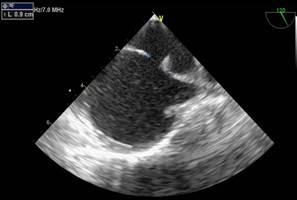

En subcostal 4 cámaras se observa CIA de 7 mm de diámetro con shunt de izquierda a derecha. (Figuras 2,3,4)

La distancia del defecto al plano valvular tricúspideo (borde anteroinferior) es de 11 mm. (Figura 5 )